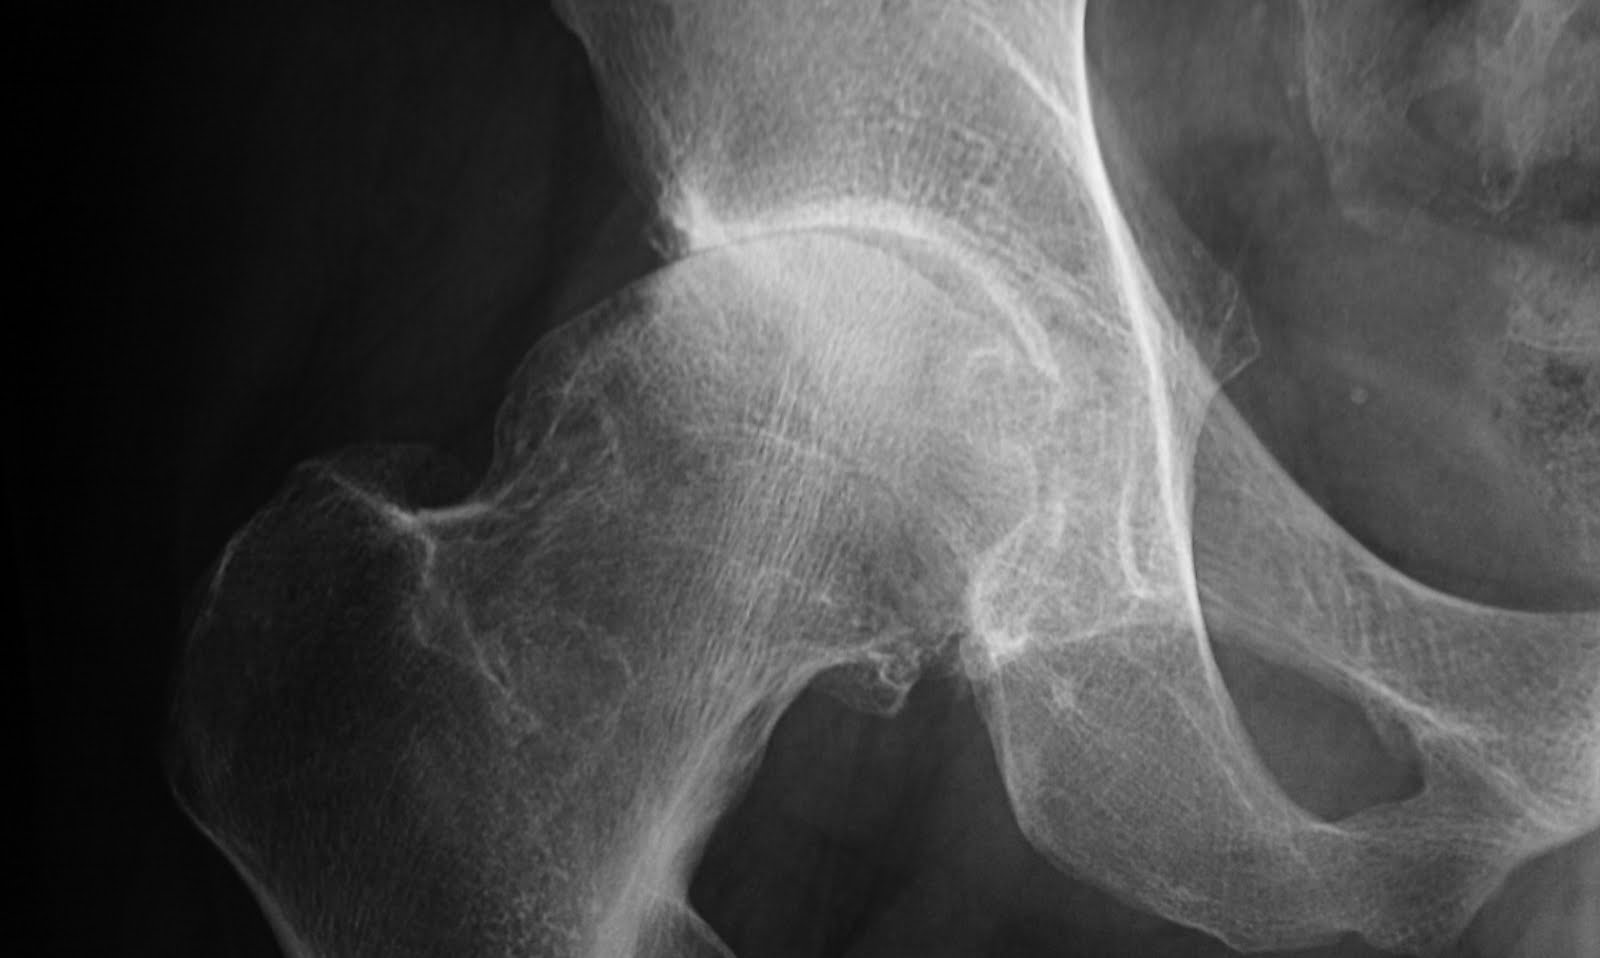

Gun Stock Deformity Hip . It was first described by dr. a decreased head/neck offset has been recognized on ap pelvic views and labeled as pistol grip deformity. The aim of the study. dr tushar agarwalcabitus varus the gun stock present by wiroc associated with. early hip joint degeneration is a common clinical presentation and preexisting abnormal joint morphology is a risk factor for its. pistol grip deformity describes the abnormal shape of the hip joint. Stulberg and associates back in.

early hip joint degeneration is a common clinical presentation and preexisting abnormal joint morphology is a risk factor for its. The aim of the study. pistol grip deformity describes the abnormal shape of the hip joint. dr tushar agarwalcabitus varus the gun stock present by wiroc associated with. Stulberg and associates back in. a decreased head/neck offset has been recognized on ap pelvic views and labeled as pistol grip deformity. It was first described by dr.

Gun Stock Deformity Hip early hip joint degeneration is a common clinical presentation and preexisting abnormal joint morphology is a risk factor for its. dr tushar agarwalcabitus varus the gun stock present by wiroc associated with. It was first described by dr. early hip joint degeneration is a common clinical presentation and preexisting abnormal joint morphology is a risk factor for its. pistol grip deformity describes the abnormal shape of the hip joint. a decreased head/neck offset has been recognized on ap pelvic views and labeled as pistol grip deformity. Stulberg and associates back in. The aim of the study.